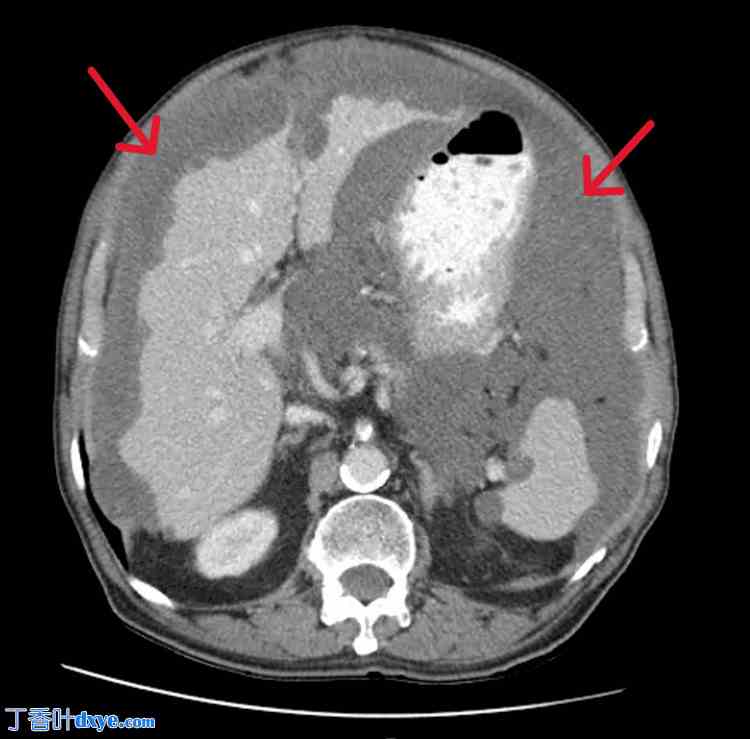

图2. 腹部CT扫描(轴向面)。

红色箭头指向假粘液瘤的病变部位。